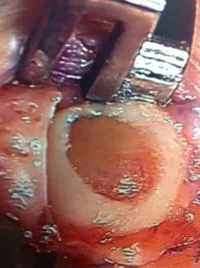

Pics of nodules removed during scope.  A separate incision had to be made to remove the nodules due to the size.